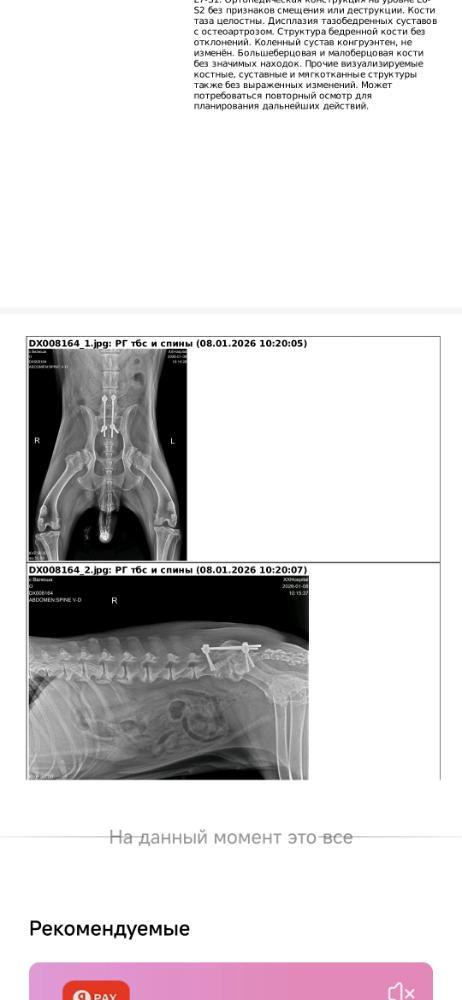

Опять испытание для Валюши - н/о молочной железы, готовимся к операции😢Девчушке нужна наша помощь и поддержка! Куратор Вячеславовна